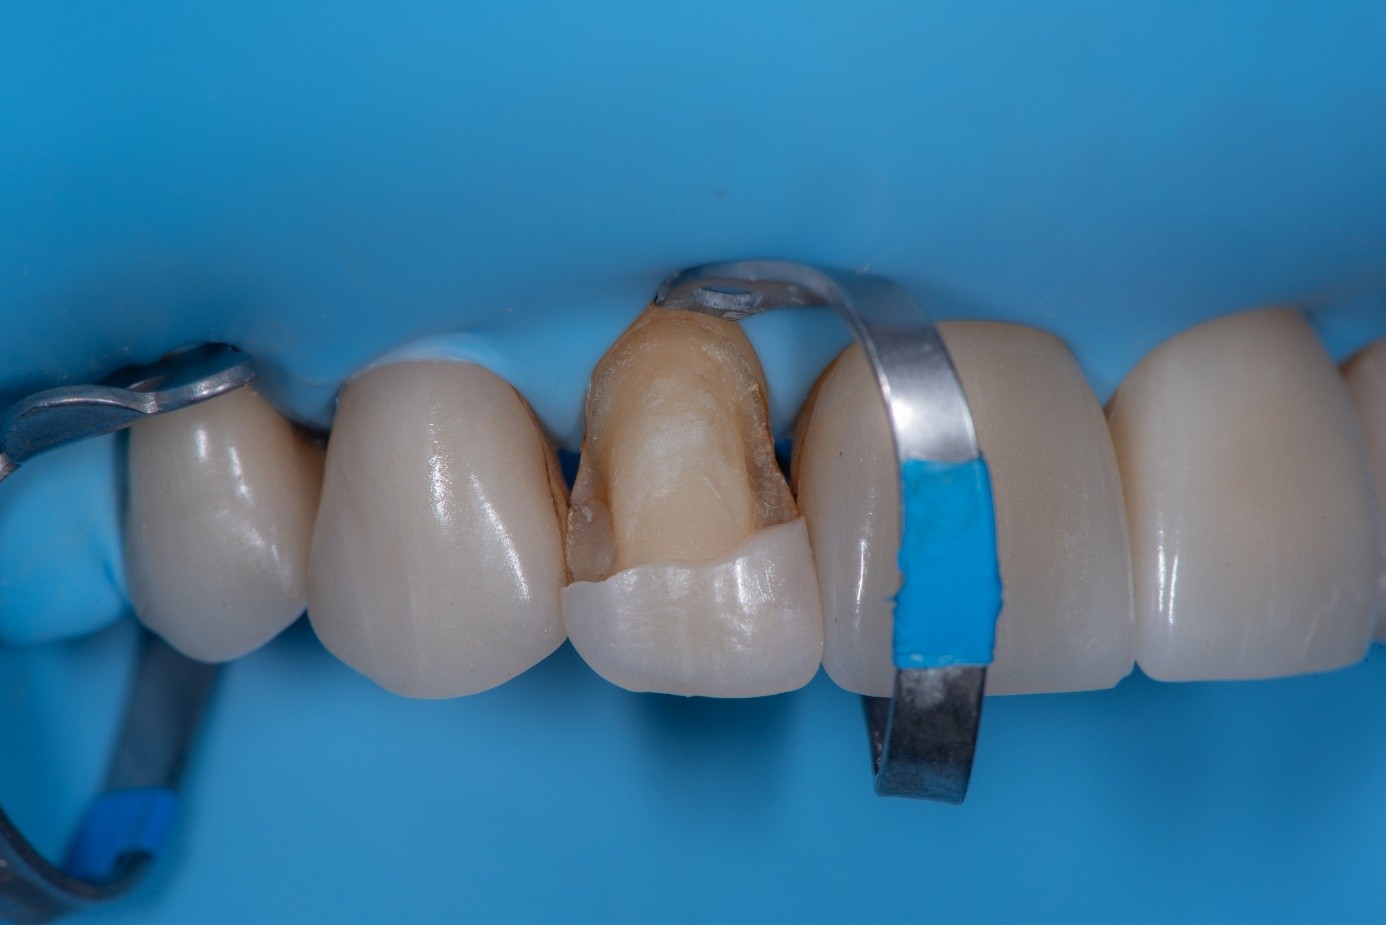

Case 2: Composite Facing Fracture

This case involved a patient with generalized mild anterior wear and an existing composite restoration on the maxillary left central incisor. The restoration extended from the middle third to the incisal edge and had excellent shade match and no marginal discoloration. The patient presented with a fractured central mesial portion of the composite (Figure 14 through Figure 16). Examination revealed a mixed failure pattern: Some adhesive and composite remnants remained on the tooth surface, while the fractured piece showed no residue internally. This finding suggested that the weak point was at the interface between composite and adhesive layer, with a minor cohesive component within the composite itself (Figure 17).

After achieving rubber dam isolation, the fractured composite segment was first air-abraded with aluminum oxide particles to clean and roughen the surface. It was then etched with phosphoric acid for 60 seconds, rinsed, dried, and treated with silane to enhance chemical adhesion (Figure 18 through Figure 20).8,9

The tooth surface was similarly air-abraded to remove biofilm and aged resin remnants, then selectively etched with phosphoric acid. Silane was applied intraorally to the exposed composite surface to promote bonding between the old and new composite layers.10 Following this, a universal bonding agent was applied to both the tooth surface and the fractured composite segment (Figure 21 through Figure 24).

(14.) Intraoral view showing the fractured ceramic fragment positioned in place. The piece fits well, although minor gaps are present between the margins due to slight material loss, which can be restored using luting composite.

Figure 14

(15.) Intraoral view showing the fractured ceramic fragment positioned in place. The piece fits well, although minor gaps are present between the margins due to slight material loss, which can be restored using luting composite.

Figure 15

(16.) Intraoral view showing the fractured ceramic fragment positioned in place. The piece fits well, although minor gaps are present between the margins due to slight material loss, which can be restored using luting composite.

Figure 16